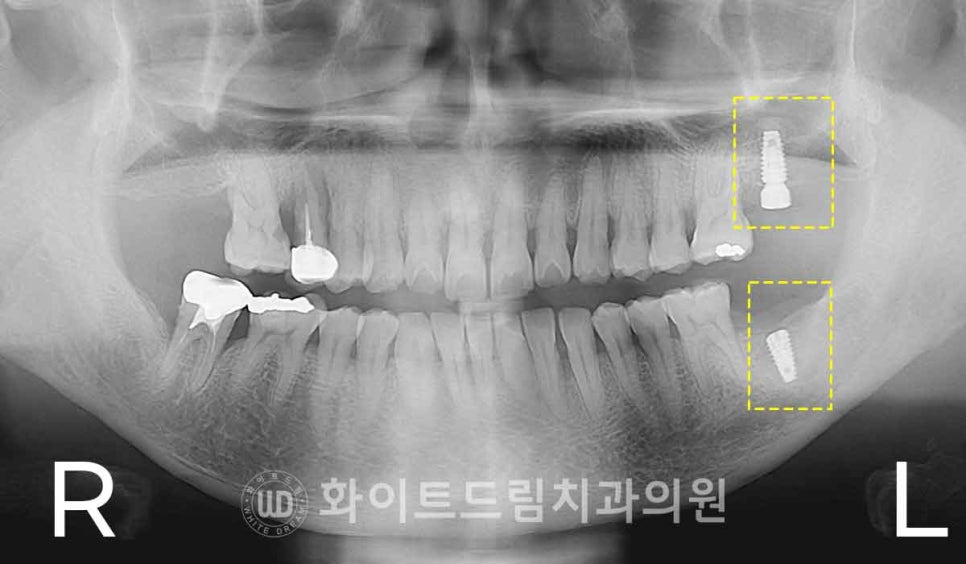

환자분의 경우 오른쪽 상·하악 어금니는 임플란트가 바로 식립 가능한 상태였지만,

▲ 왼쪽 상/하악 임플란트 수술, 강남역치과 임플란트 수술 일자 : 16.12.27

그래서 치료 계획을

오른쪽 상·하악 어금니는 내원 당일 바로 수술을 진행하고,

왼쪽 상악 어금니는 발치 후 약 3개월의 치유 기간을 거친 뒤

임플란트를 식립하는 방식으로 나누어 진행하게 되었습니다.